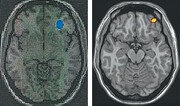

인터넷 게임 중독자의 뇌가 마약 중독자의 뇌와 유사하게 활동한다는 사실을 국내 연구진이 밝혀냈다. 김상은 분당서울대병원 핵의학과 교수팀은 “양전자방출단층촬영(PET) 기법으로 인터넷 게임 정상 사용자 9명과 게임 과다 사용자 11명의 대뇌 포도당 대사 등을 측정한 결과 인터넷 게임 과다 사용자는 오른쪽 안와 전두피질, 왼쪽 미상핵, 오른쪽 도회의 기능이 정상인보다 떨어진다”고 9일 밝혔다. 안와 전두피질, 미상핵, 도회는 각각 충동 조절, 보상 처리, 중독을 담당하는 인지 기능을 관장하는 대뇌영역이다. 인터넷 게임을 과도하게 하면 뇌의 기능이 떨어지고 이를 활성화하기 위해 특정 부위의 포도당 대사가 활발해진다. 약물 남용, 도박 중독, 충동조절장애를 겪는 환자들의 뇌도 유사한 작동 기제를 보인다. 김 교수의 연구 결과는 내년 해외 과학저널인 ‘씨엔에스 스펙트럼스(CNS Spectrums)’에 게재될 예정이다. 우경임 기자 woohaha@donga.com}